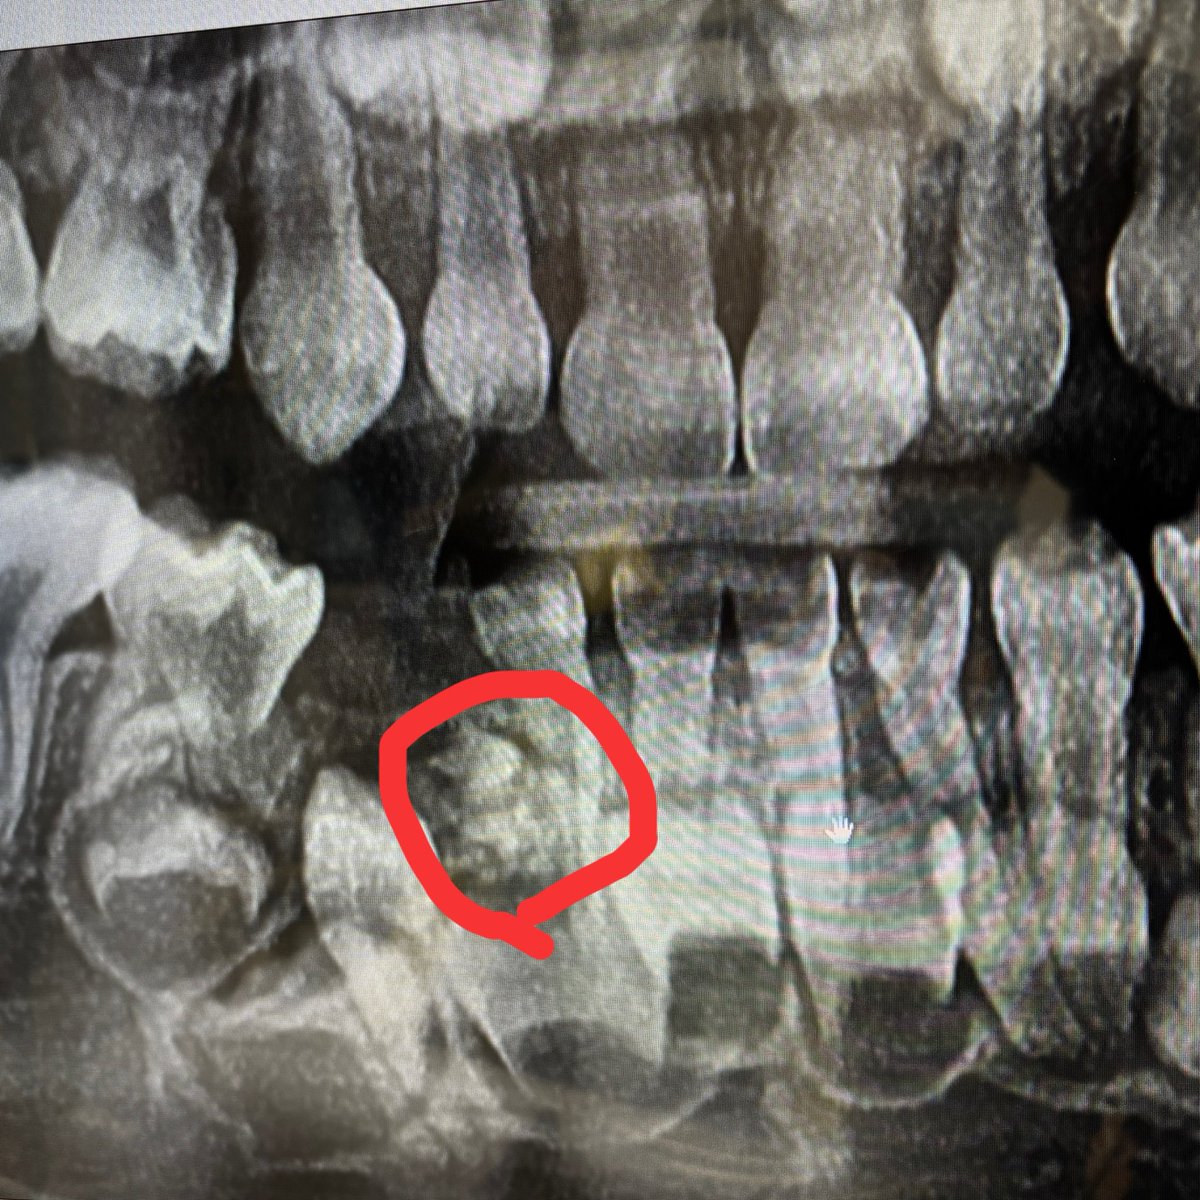

集合性歯牙腫かな

子どもの歯に詳しい人どうか 歯が生えてこず、もう少し待ちましょうで様子見てたのね。で、結果「腫瘍が邪魔してる。もう乳歯もダメになってる。全身麻酔で腫瘍と乳歯を取りましょう」言われたんだけどこの腫瘍の名前なんだっけ。悪いもの? パニックなってしまって色々忘れてしまった。 赤丸が腫瘍